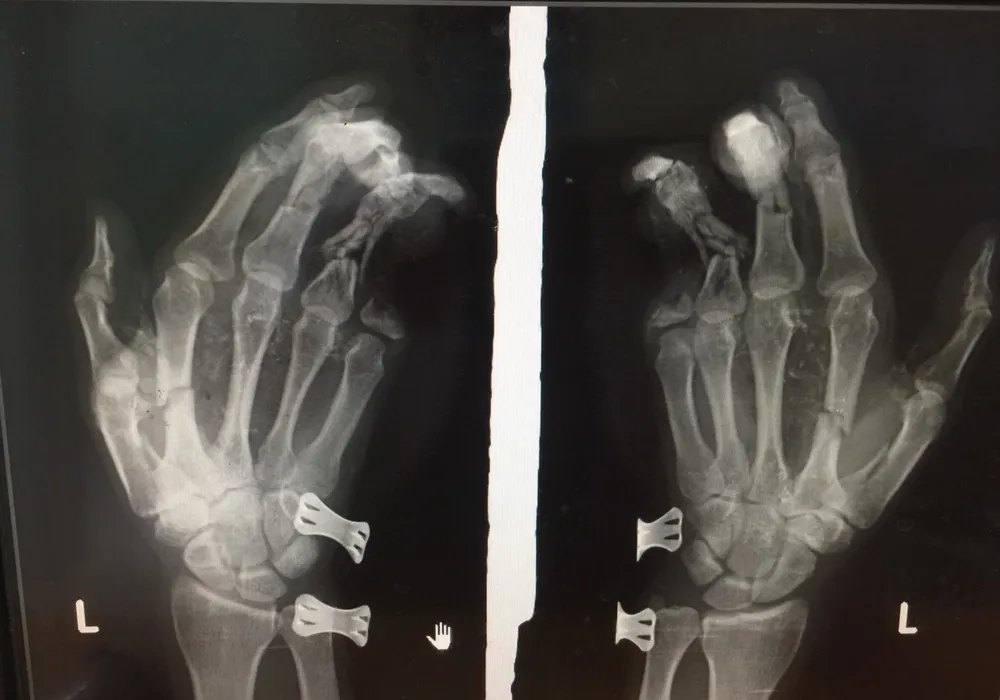

Điện thoại phát nổ khi đang sạc khiến nam thanh niên bị dập nát bàn tay  ảnh 1 Phim chụp bàn tay của nam thanh niên bị tổn thương do điện thoại phát nổ

Hậu quả, vụ nổ làm bàn tay trái của anh Duy dập nát, tổn thương nặng và ngón út bị cụt mất 2 đốt.

Tại bệnh viện, nam thanh niên được sơ cứu, chụp phim và đưa vào phòng mổ phẫu thuật khâu lại viết thương.